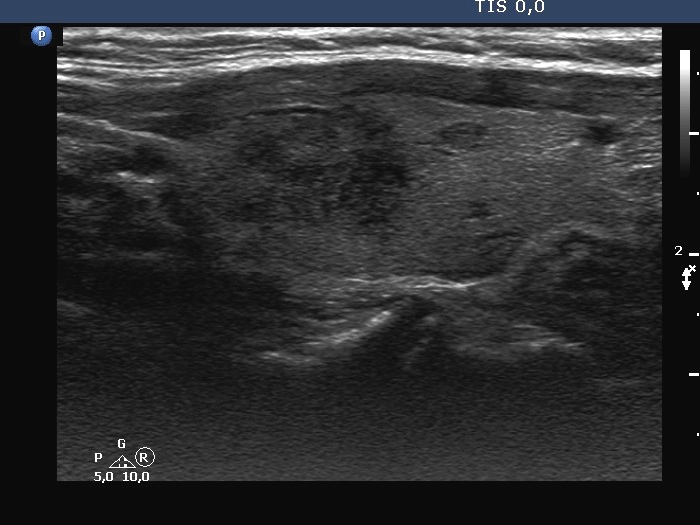

First examination (first row of images):

Ultrasonography. The thyroid was minimally hypoechoic. There was a small, discrete lesion in the upper pole of the right lobe. The left lobe had a larger and several tiny hypoechogenic lesions. The large lesion presented partly blurred, partly lobulated margins.

Cytology was performed from the large hypoechoic lesion in the left lobe and resulted in subacute, de Quervain's thyroiditis.

2. The hypoechoic lesion in the left lobe had lobulated, spiculated and not blurred margins as in the usual case of de Quervain's thyroiditis.